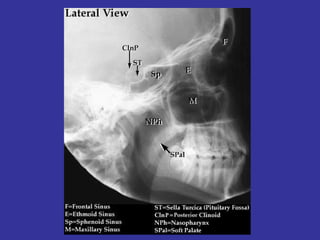

ANATOMY / DEVELOPMENT 4 Sinuses: Maxillary, Ethmoidal, Frontal, Sphenoidal MAXILLARY  SINUSES DEVELOPS  DURING  3rd & 4th GESTATIONAL  MONTH  WITH PNEUMATIZATION BETWEEN  BIRTH AND 12 MONTHS OF AGE ETHMOID   SINUSES DEVELOPS  DURING  3 rd  & 4 th  GESTATIONAL  MONTH. IS PRESENT AT BIRTH, DEVELOPING  UNTIL 12-14 YEARS OF AGE SPHENOID   SINUS DEVELOPED BY AGE 8-10 YEARS FRONTAL   SINUS DEVELOPS DURING  5 th  AND 6 th  YEAR.

In the sides of the nasal septum, there is 3 shelf-like structures where discharge is drain and is called  Turbinates  MAXILLARY ANT. ETHMOID  MIDDLE MEATUS FRONTAL POST. ETHMOID   SUPERIOR MEATUS SPHENOID LACRIMAL DUCTS   INFERIOR MEATUS (Largest and most visible)

ANATOMY / DEVELOPMENT4 Sinuses: Maxillary, Ethmoidal, Frontal, Sphenoidal MAXILLARY SINUSES DEVELOPS DURING 3rd & 4th GESTATIONAL MONTH WITH PNEUMATIZATION BETWEEN BIRTH AND 12 MONTHS OF AGE ETHMOID SINUSES DEVELOPS DURING 3 rd & 4 th GESTATIONAL MONTH. IS PRESENT AT BIRTH, DEVELOPING UNTIL 12-14 YEARS OF AGE SPHENOID SINUS DEVELOPED BY AGE 8-10 YEARS FRONTAL SINUS DEVELOPS DURING 5 th AND 6 th YEAR.

In the sidesof the nasal septum, there is 3 shelf-like structures where discharge is drain and is called Turbinates MAXILLARY ANT. ETHMOID MIDDLE MEATUS FRONTAL POST. ETHMOID SUPERIOR MEATUS SPHENOID LACRIMAL DUCTS INFERIOR MEATUS (Largest and most visible)